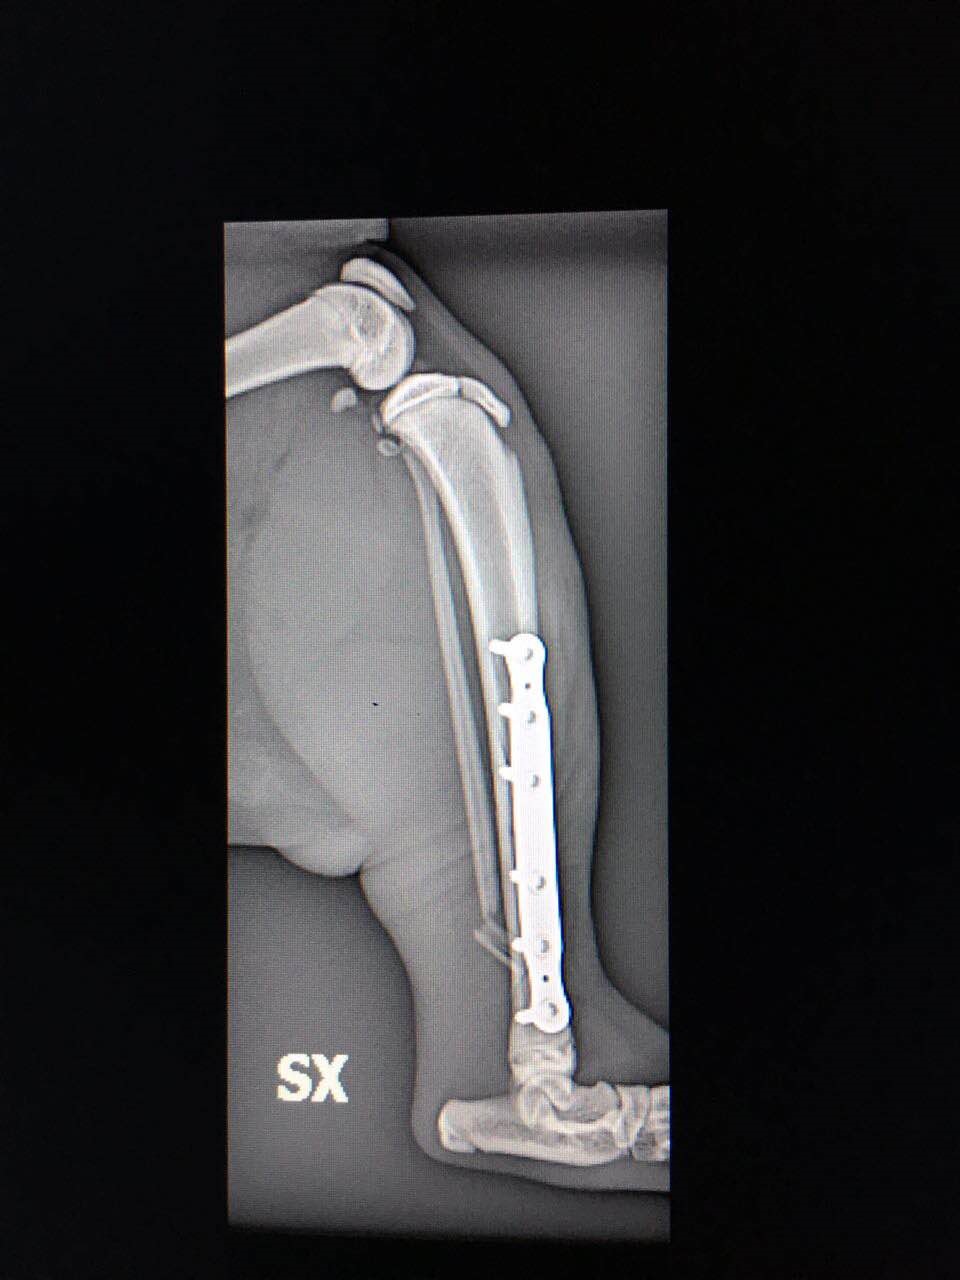

Inoltre, la scelta di mezzi di sintesi di ultima generazione come le Placche a Stabilità Angolare o i Fissatori Esterni Radio Trasparenti per i cani di taglia “toy”, permettono il miglior confort possibile per l’animale consentendone una guarigione e recupero della funzione motoria in tempi molto brevi.

A titolo esemplificativo, riportiamo due immagini